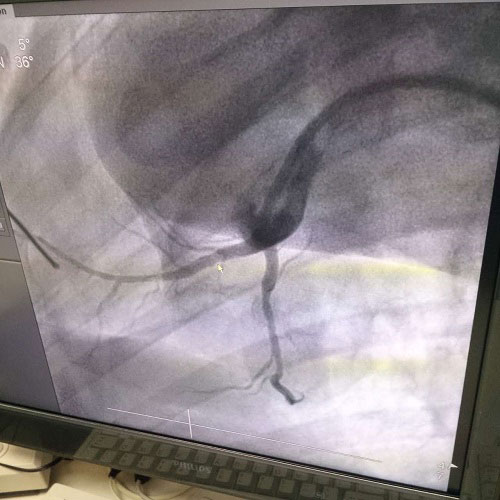

近年來(lái),隨著現(xiàn)代醫(yī)療技術(shù)的發(fā)展和醫(yī)療設(shè)備的日趨完善,介入性支架治療已經(jīng)成為介入心血管療法的一種主要手段。血管介入技術(shù)是在醫(yī)學(xué)影像設(shè)備的導(dǎo)引下,利用穿刺針、導(dǎo)絲、導(dǎo)管等器械經(jīng)血管途徑進(jìn)行診斷與治療的操作技術(shù),已經(jīng)成為治療各種危險(xiǎn)人類健康疾病的最佳方法之一。

生物全降解鎂合金藥物洗脫支架是我由公司自主立項(xiàng)研發(fā)、主要工藝技術(shù)完全自主,具有完全自主知識(shí)產(chǎn)權(quán)。并且可行性強(qiáng),前期研發(fā)基礎(chǔ)扎實(shí),市場(chǎng)需求迫切,實(shí)施風(fēng)險(xiǎn)可控,屬全球同行業(yè)領(lǐng)先技術(shù),填補(bǔ)國(guó)內(nèi)技術(shù)發(fā)展空白,符合國(guó)家產(chǎn)業(yè)發(fā)展政策,社會(huì)、經(jīng)濟(jì)效益巨大。目前鎂合金藥物支架已進(jìn)入動(dòng)物實(shí)驗(yàn)階段,植入動(dòng)物體內(nèi)一個(gè)月之后效果良好。